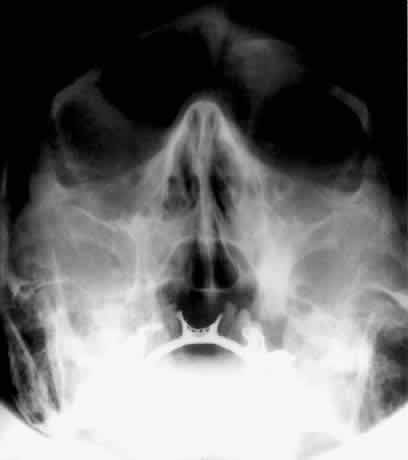

WATERS PROJECTION

In an attempt to improve the visualization of the maxillary and ethmoid sinuses, in 1915 Waters and Waldron7 described a radiographic projection (Fig. 2) that eliminated the overlapping shadows of the dense petrous ridge of the temporal bone. Waters projection is created by placing the chin of the patient on the x-ray cassette with the canthomeatal line (the line that connects the lateral canthus and the external auditory meatus) at 37 degrees to 45 degrees.5,6 This orientation is accomplished if the nose of the patient is approximately 0.5 to 1.5 cm above the x-ray plate.7,8 A mnemonic is—the patient raises the chin up to sip water.

Fig. 2. A. Schematic showing positioning for a Waters projection. (CM, canthomeatal line; CR, central ray) B. Radiograph of a Waters projection. The petrous ridge lies below the maxillary sinus. (a, frontal sinus; b, medial orbital wall; c, innominate line; d, inferior orbital rim; e, orbital floor; f, maxillary antrum; g, superior orbital fissure; h, zygomatic-frontal suture; i, zygomatic arch) (A; Rao VM, Gonzalez CF: Plain film radiography and polytomography of the orbit. In Gonzalez CF, Becker MH, Flanagan JC [eds]: Diagnostic Imaging in Ophthalmology, pp 1–7. New York, Springer Verlag, 1986)

Waters view provides the best image of the maxillary antrum and good images of the orbital rim, orbital floor, zygomatic bones and arches, lesser wing of the sphenoid, and infraorbital foramen. This view is useful to the clinician in orbital floor fracture assessment because of the clear image of the orbital floor and the underlying maxillary sinus. The floor of the orbit should form a continuous radiographic line with the lateral wall of the orbit. Confusion can occur regarding the location of the orbital floor and its relationship to the orbital rim. The orbital floor is located inferior to the orbital rim not in the same plane, because of the orientation of the patient's head in Waters projection. A soft tissue density in the roof of the maxillary sinus or opacification of the floor of the sinus suggests an orbital floor disruption.